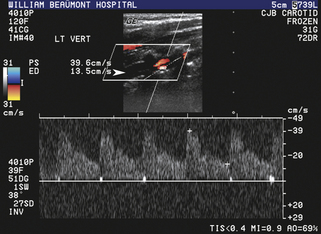

Уменьшенный поток

У пациентов с доминирующей позвоночной артерией недоминирующая, анатомически маленькая позвоночная артерия может демонстрировать характеристики кровотока с повышенным сосудистым сопротивлением со снижением скорости кровотока на пике систолы и во время диастолы. В более тяжелых случаях гипопластической, атретичной (диаметр просвета менее 2 мм) позвоночной артерии, которая может встречаться у 15% пациентов, сосудистое сопротивление по ходу сосуда может быть настолько повышено, что спектральная допплеровская волна приобретает характеристики почти полной дистальной окклюзии (т.е. отсутствие обнаруживаемого диастолического потока; рис. 11-14 ). Тяжелая обструктивная болезнь проксимальных отделов позвоночных артерий также может быть причиной снижения кровотока в вертебробазилярной системе и цереброваскулярных симптомов. В таких случаях форма волны спектральной допплеровской скорости демонстрирует форму волны tardus-parvus, характерную для затухания, форму волны с задержкой начала округлого, плохо выраженного систолического пика, плохой антеградный поток во время диастолы и значительное снижение скорости на протяжении всего сердечного цикла (рис . 11-15 ). Если в позвоночной артерии наблюдаются затухающие допплеровские сигналы, необходимо провести тщательное дуплексное ультразвуковое исследование проксимального сегмента и места расположения пораженной позвоночной артерии, чтобы определить локализацию и тяжесть любого обструктивного поражения, которое может присутствовать.

РИСУНОК 11-15. Уменьшение кровотока в средней позвоночной артерии вследствие проксимального стеноза. Кривая скорости имеет классическую форму tardus-parvus с округлым, плохо выраженным систолическим пиком и снижением скорости на протяжении всего сердечного цикла. (Пиковая систолическая скорость [ПСВ] составляет 13 см/сек.)